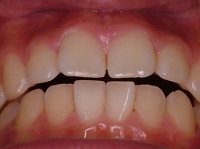

さらに,この下顎位にて上顎の後方歯および下顎にもワイヤー矯正を施しバランス矯正治療は終了となりました(非抜歯矯正)↓.

.

⇒

↑矯正治療中 ↑矯正治療後

動的治療期間28ヶ月29回/費用概算65万円.